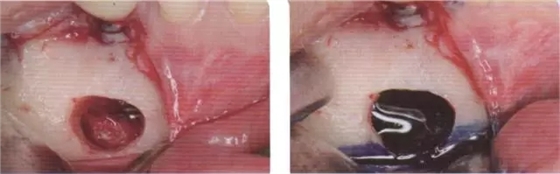

在口腔外科治療中, 拔牙后疼痛是最常見的并發(fā)癥,其成因有很多種因素5。通過拔牙造成牙糟骨創(chuàng)傷的因素, 除了患者特定因素外, 其它的還有如一般健康狀況、藥物、尼古丁和酒精5,15。由于感染調(diào)節(jié),使細菌滲透到牙糟骨內(nèi)并形成骨炎,其中患者會因由此所造成的神經(jīng)炎而產(chǎn)生強烈的癥狀。在序列拔牙中, 術(shù)后疼痛的出現(xiàn)與單顆牙拔除相比卻鮮有被報道15。然而在即刻種植后, 這可能會因患者要求拔出種植體而導(dǎo)致產(chǎn)生劇烈的疼痛; 或者在另一方面會顯示, 造成種植體底端出現(xiàn)種植體周圍炎癥狀。如果出現(xiàn)這樣的情況,是非常難以治療的,因為感染的病灶通常位于舌側(cè),而通過外科手段進入骨溶解區(qū)兒乎是不可能的(圖1至7)。

圖1 圖2

圖1 患者46牙根管再治療失敗,出現(xiàn)根尖炎癥,準備拔除做即刻種植

圖2 小視野CBCT圖像顯示種植修復(fù)一年后的骨容解情況